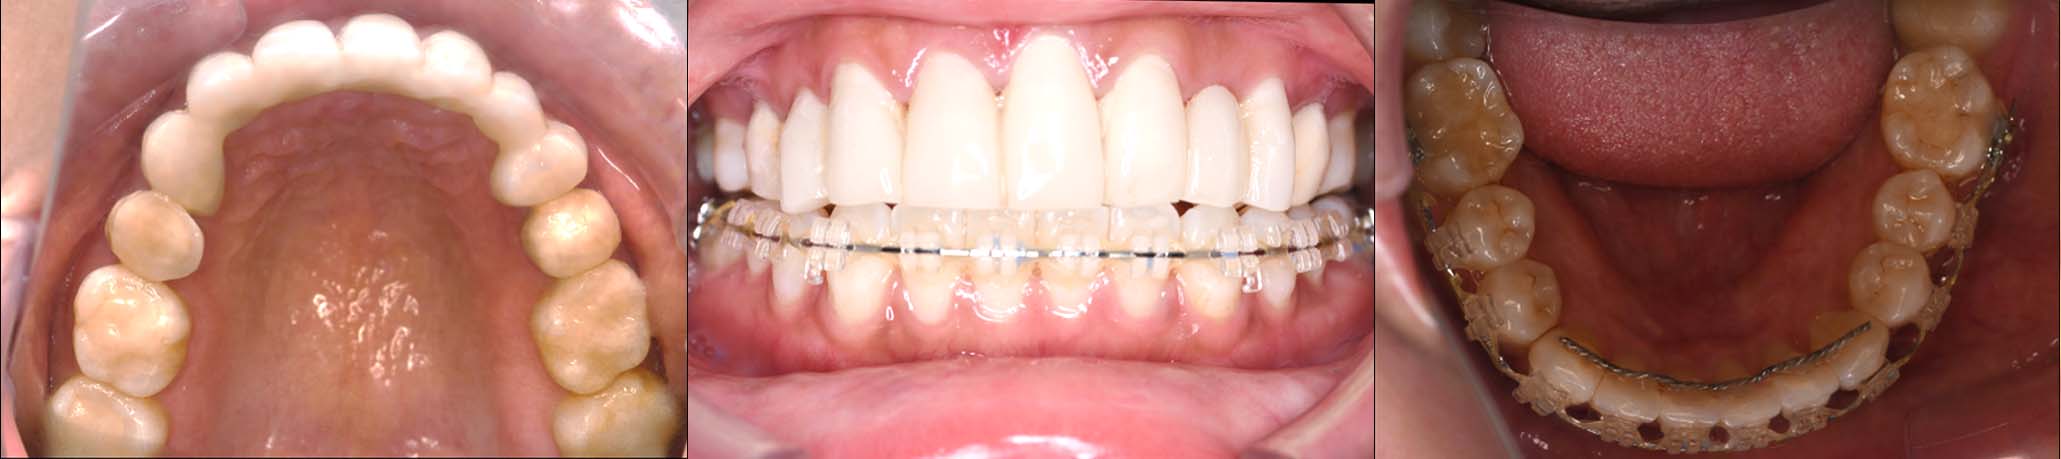

スプリント使用後、

補綴治療をした症例

治療内容 ①スプリントを装着

②副子を装着

③2024年4月 口腔内反映開始

④副子を入れた状態の所まで咬合を挙上

(バイトアップ)

⑤2024年5月 上顎前歯部8本へ仮歯(TEK)

を装着

2024年 10月 下顎MTM開始